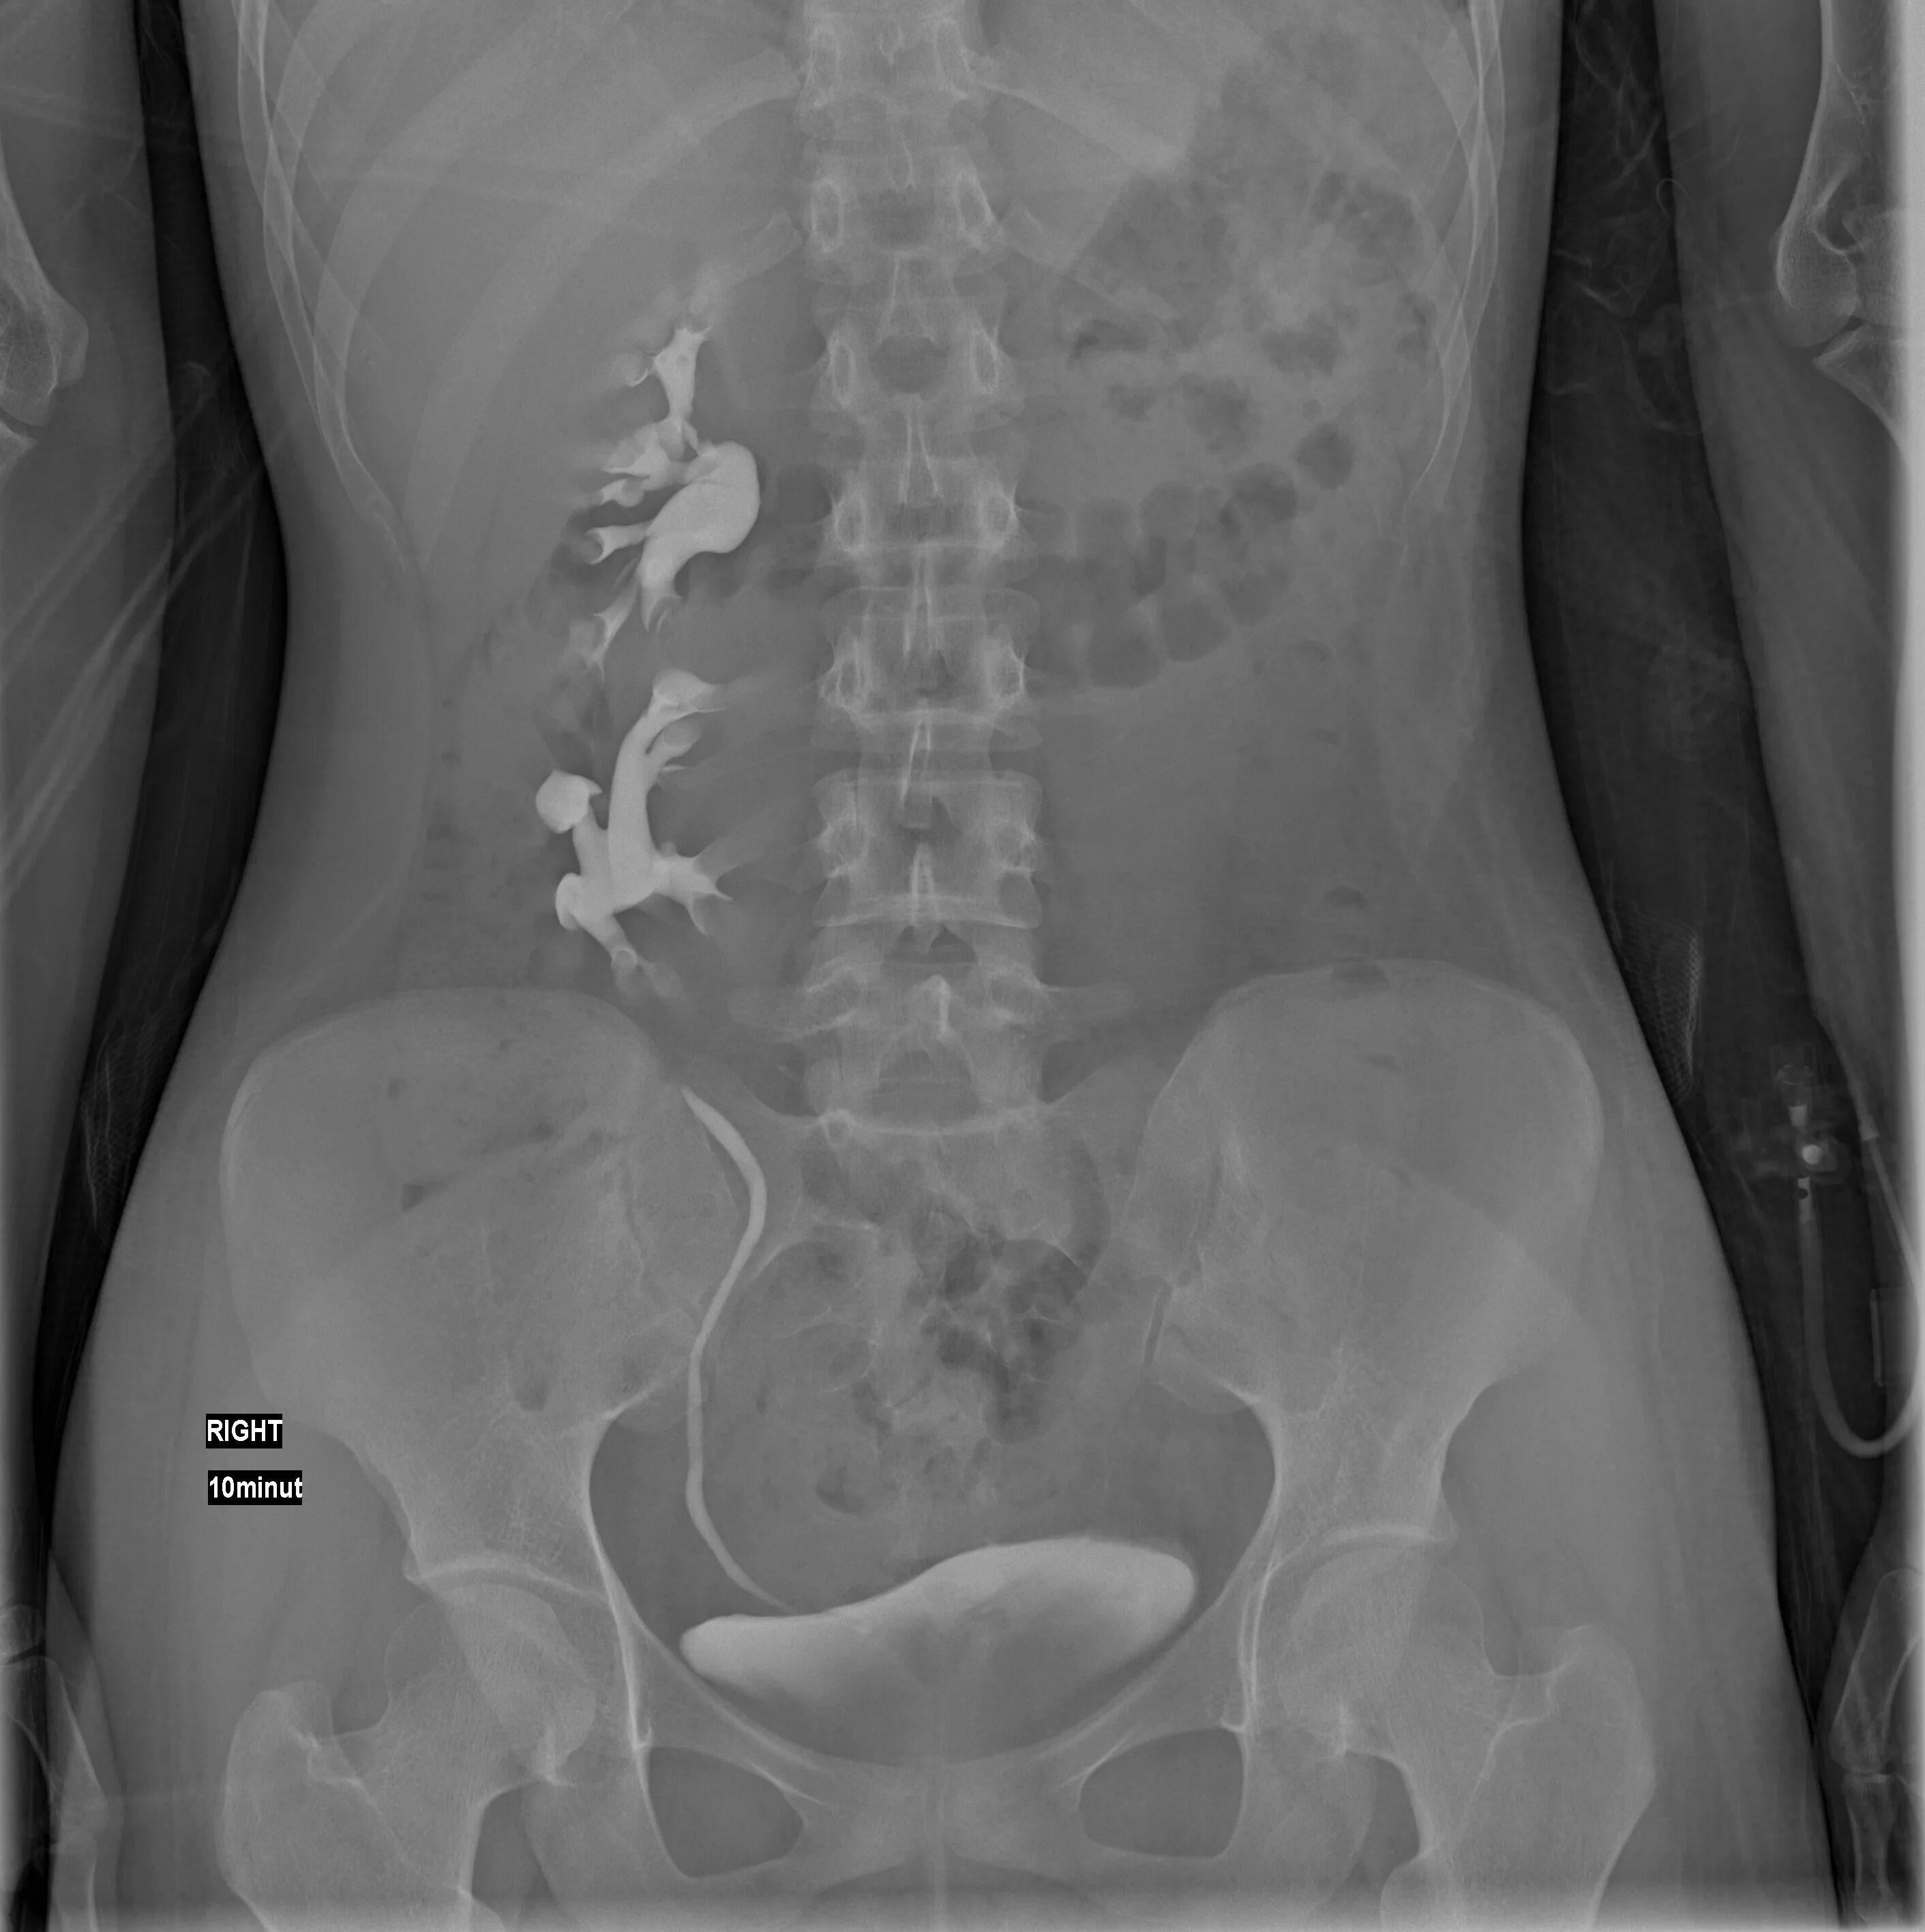

Урография с контрастом